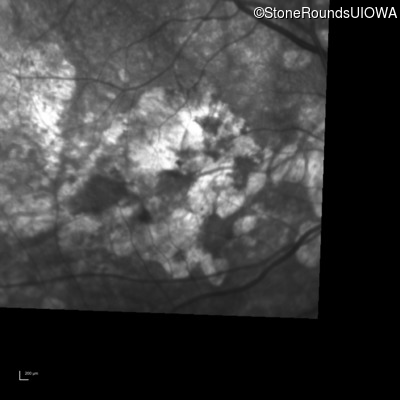

Infrared Fundus Photograph - Right - 20/200 +2

Exemplar